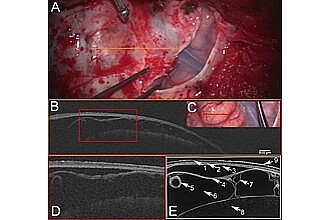

Die OCT-Bildgebung beruht auf der Erfassung von rückgestreutem Nahinfrarotlicht und ist daher für biologisches Gewebe unschädlich. Seine physikalischen Eigenschaften ermöglichen die Integration in ein Mikroskop. Dies ermöglicht ein berührungsloses dreidimensionales Scannen von Gewebe in Echtzeit im Sichtfeld des Chirurgen. Die Eindringtiefe hängt von der optischen Gewebedichte ab. Mit ca. 4000 µm in der menschlichen Großhirnrinde erfüllt es die mikrochirurgischen Anforderungen.

Insbesondere bietet die OCT eine noch nie dagewesene axiale räumliche Auflösung von 1 - 15 µm, die an die Auflösung der konventionellen Histopathologie heranreicht. Jüngste Fortschritte in der Optik und Bildverarbeitung wie die automatische serielle Schnittdarstellung des polarisationsempfindlichen OCT (asPSOCT) und die Speckle-Modulation haben die Bildqualität weiter verbessert und ermöglichen die Darstellung der zerebralen Kortikalisschichten in Einzelzellbreite.

Diese vielseitigen Stärken werfen ein Licht auf zukünftige Perspektiven. Unser Team validiert den intraoperativen Einsatz von mikroskopisch integriertem OCT für die Weiterentwicklung der neurochirurgischen Führung.